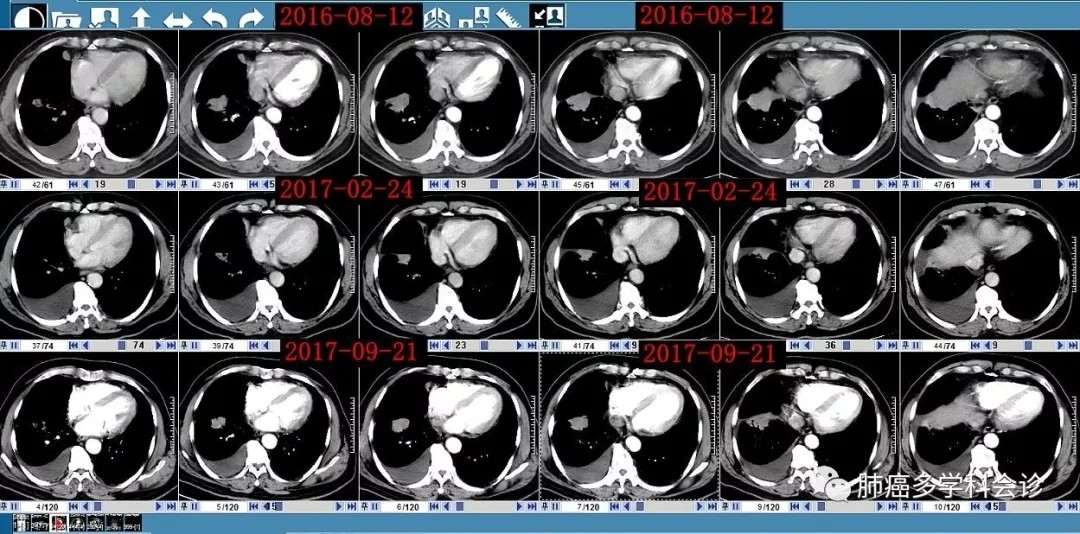

:患者早期接受化疗及后来TKI治疗期间肿瘤的变化(相对现在较缓慢):

患者在2016-08 ~ 2018-05在X省X院X科X病区先后进行了 6个双药联合方案的化疗(1-6线),最后发生腹腔淋巴结转移和腹膜腔转移,以下是该患者的化疗简史:

• 2016-08 ~ 2017-01“多西他赛+奥沙利铂”× 6 周期

• 2017-03 ~ 2017-06 “培美曲塞+奥沙利铂” × 5 周期,最后一次输液奥沙利铂过程中出现I型过敏反应(胸闷、呼吸困难、上肢与胸前皮肤红疹)。

• 2017-07 ~ 2017-10“培美曲塞+洛铂”× 3 周期。2017-09 胸腔灌注“白介素-2”

• 2017-12 ~ 2018-01 "多西他赛+吉西他滨" ×2 周期

• 2018-02 ~ 2018-03 "伊立替康+替吉奥" ×2 周期。

• 2018-04 复查 CT 示病情进展。周围血EGFR基因无突变。

• 2018-04“洛铂+依托泊苷” × 1周期。